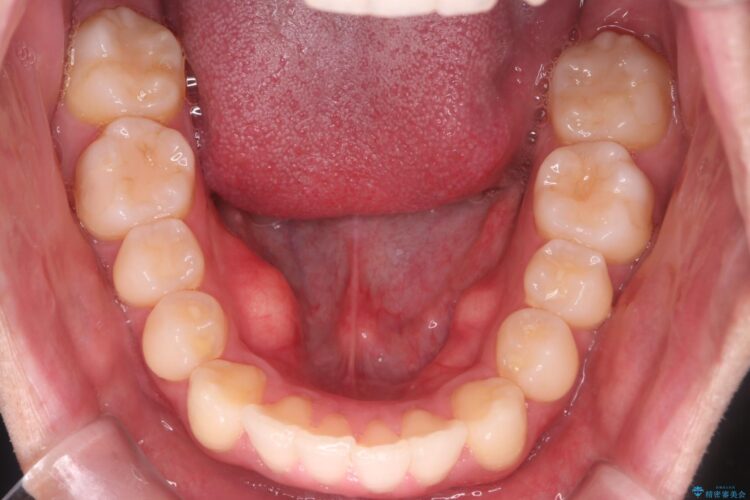

上の前歯が出ているのが気になるとご来院された患者様です。

IPR(歯と歯の間を削る処置)を行うことで、前歯の位置とがたつき整える治療計画を立てました。

患者様はシミュレーション通りに歯が動くのかと心配されていました。

可能な限り計画通りに歯を動かすために、マウスピース1枚あたりの使用時間を長めに使っていただきました。

そのため、多少治療期間が延びましたが、リファイメント(マウスピースの再発注)なしで終了することができました。